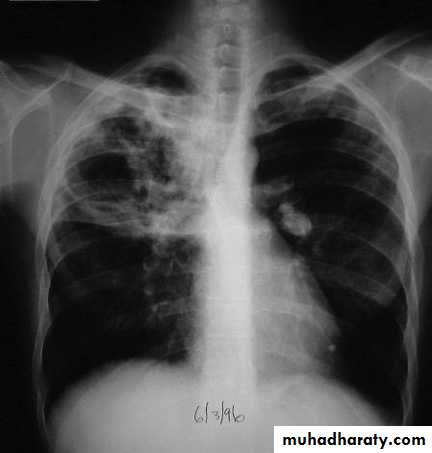

Radiological changes include

opacification in one or both of the upper lobes,

consolidation

collapse

cavitation

tuberculous pneumonia